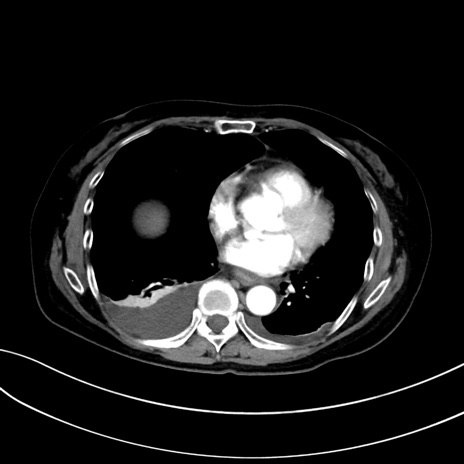

症例13 CT(横断像)1日半後